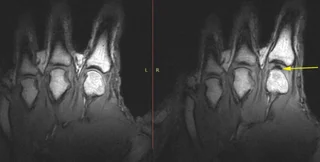

У рамках дослідження цього феномена, вчені помістили людину в апарат МРТ з датчиками на пальцях. Вони дозволили фіксувати внутрішні механізми хрускоту кісточки пальця в режимі реального часу. Тривалий час вважалося, що тріск — це результат колапсу крихітної газової бульбашки в синовіальній рідині, що оточує наші суглоби, але це не так, йдеться в дослідженні МРТ.

Насправді ж учені побачили, що процес хрускоту суглоба навпаки створював газову порожнину там, де її раніше не було.

Також процес тріскання суглобів було проаналізовано за допомогою ультразвукової технології. Ультразвук може бачити процеси, що відбуваються всередині тіла, в 100 разів швидше і виявляти речі в 10 разів менші, ніж сканери МРТ.

Команда була впевнена, що звук хрускоту суглоба і яскравий спалах на УЗД були пов'язані зі змінами тиску, пов'язаними з газовим міхуром у суглобі. Це не остаточно вирішило суперечку про формування або руйнування, але автори дослідження вважають, що побачене підтверджує теорію утворення бульбашок, а не теорію їхнього лопання.

Вчені також з'ясували, що після хрускоту порожнина з газом залишалася якийсь час, а після зникала без видимих пошкоджень суглоба. Хрускіт кісточками пальців, схоже, не змінив відстань між суглобами в довгостроковій перспективі, але варто зазначити, що в дослідженні брав участь тільки один учасник.